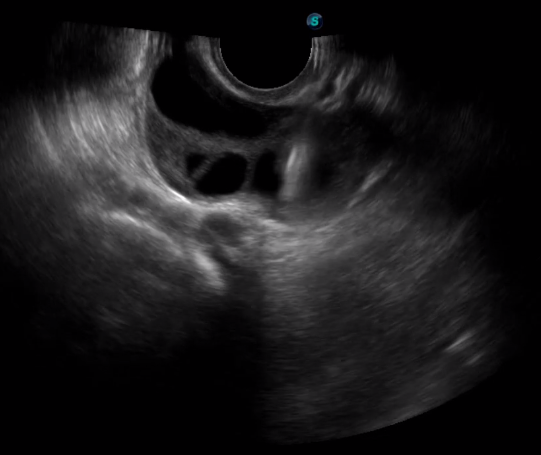

取卵臨床圖